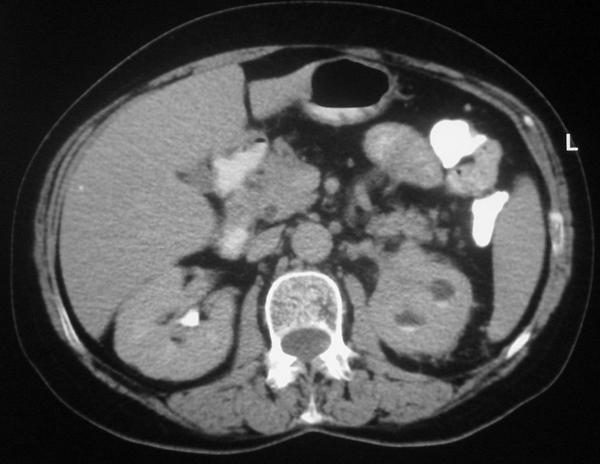

We present a case of a 68-year-old woman who underwent a computed tomography scan of the abdomen in the work-up for recently diagnosed hypertension. A non-enhancing left renal sinus mass was detected extending to the para-aortic space. The initial diagnosis was that of a tumor of the collecting system. Nephro-ureterectomy was performed and the pathology results revealed changes of chronic pyelonephritis.

我们呈现了一例68岁女性患者,其因近期诊断为高血压而接受腹部计算机断层扫描。检查发现一个无强化的左肾窦肿块延伸至腹主动脉旁间隙。初步诊断为集合系统肿瘤。实施了肾输尿管切除术,病理结果显示为慢性肾盂肾炎改变。